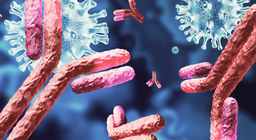

The immune system, the body’s first line of defense protects us from possibly harmful or foreign invaders.